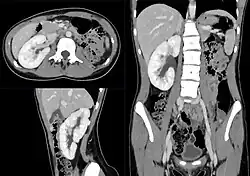

Klinik

Bei einseitigem Fehlen einer Niere übernimmt die andere Niere als Einzelniere komplett die Funktion und vergrößert sich dazu bereits intrauterin auf das Volumen zweier Nieren. Klinisch besteht aufgrund der normalen Nierenfunktion keine Auffälligkeit.

Eine beidseitige Agenesie wird durch das Oligohydramnion frühzeitig in der Ultraschalluntersuchung auffällig, eine einseitige kann beim Feinultraschall erkannt werden, aber auch lebenslang unerkannt bleiben.